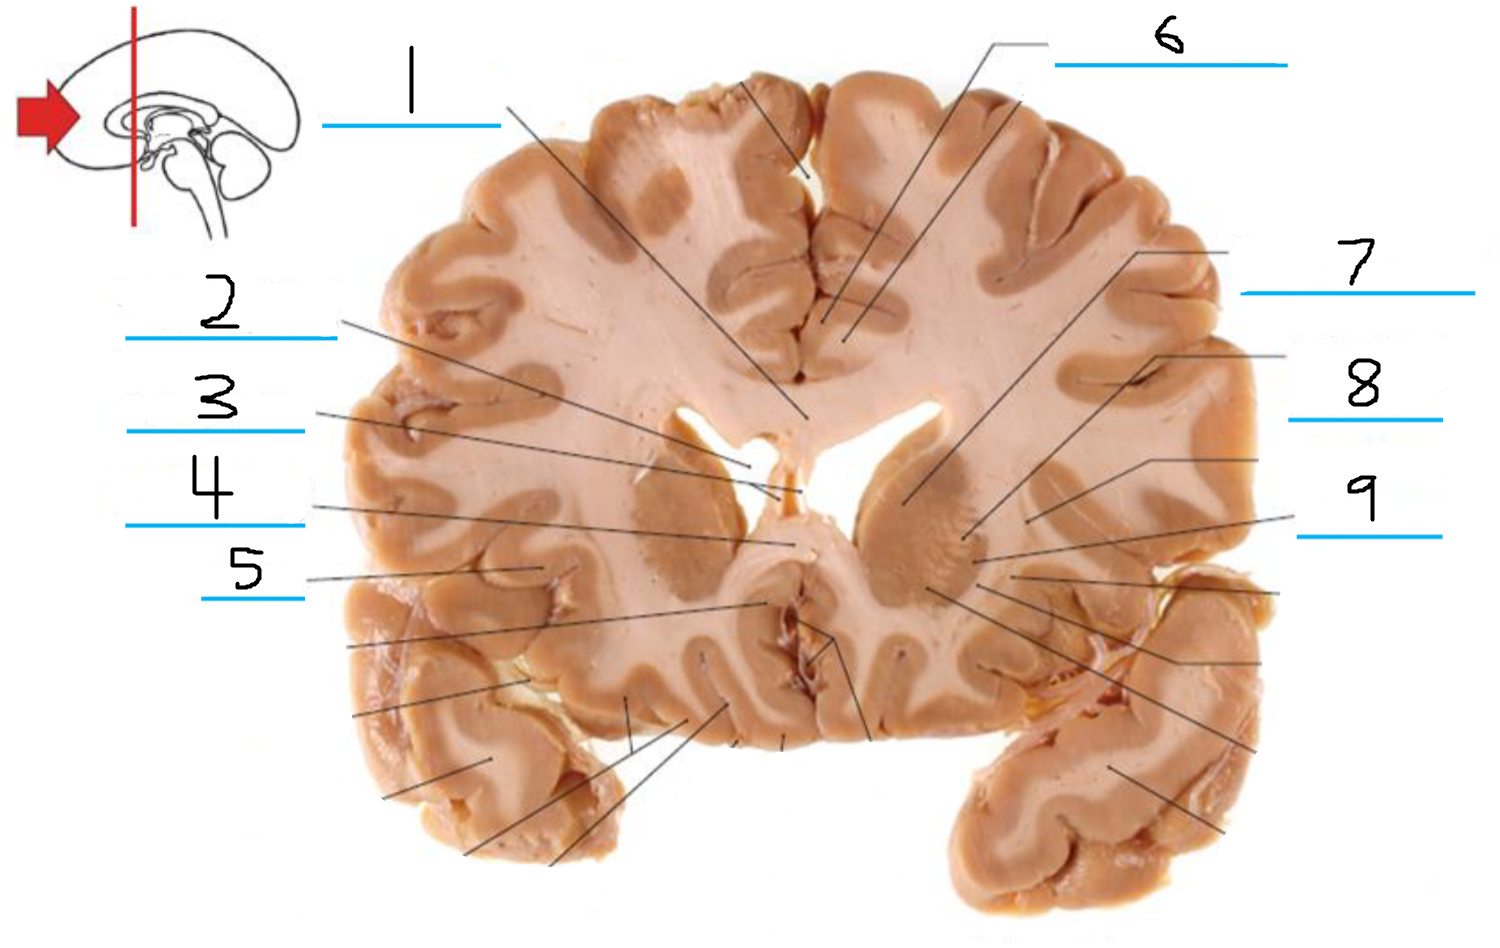

#1 is the:

Corpus Callosum

#2 is the:

Lateral Ventricle

#3 is the:

Septum Pellucidum

#4 is the:

#5 is the:

Insula

#6 is the:

Cingulate Gyrus

#7 is the:

Caudate

#8 is the:

Internal Capsule

#9 is the:

Putamen